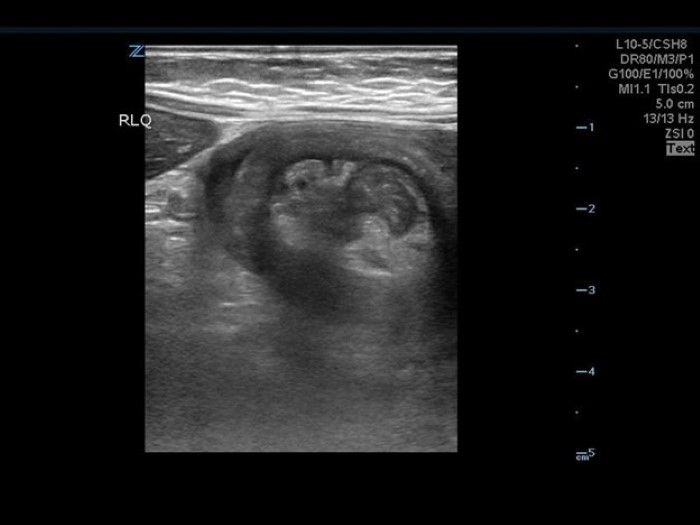

The linear probe is placed in the RLQ in the transverse position with indicator to the patient’s right. Identify the psoas muscle and iliac vessels lying medial. Once these structures are visualized, slide lateral and look superficially to identify the cecum. (Figures 1a,1b 1) Use graded compression-progressive increase and decrease of pressure to move any gas out of view. Keeping the lateral edge of the abdominal cavity in view (Figure 2), the ultrasound probe should slide cranial in traverse plane, visualizing the ascending colon until the hepatic flexure.  In this location, the colon turns just medial to the liver with the kidney deep in the view. (Figure 3) This is the most common location to identify ileocolic intussusception. If no tissue mass is identified, the probe should be turned to the sagittal plane with indicator toward the head (to keep the colon visualized in the transverse view) and moved across the transverse colon continuing to use graded compression to look for a tissue mass consistent with intussusception. Once at the splenic flexure (Figure 4), the probe should be transitioned back to the transverse orientation to interrogate the descending colon.

10-2024 Article7-4.jpgFigure 4 LUQ Colon perimeter with kidney and edge of peritoneum in view.